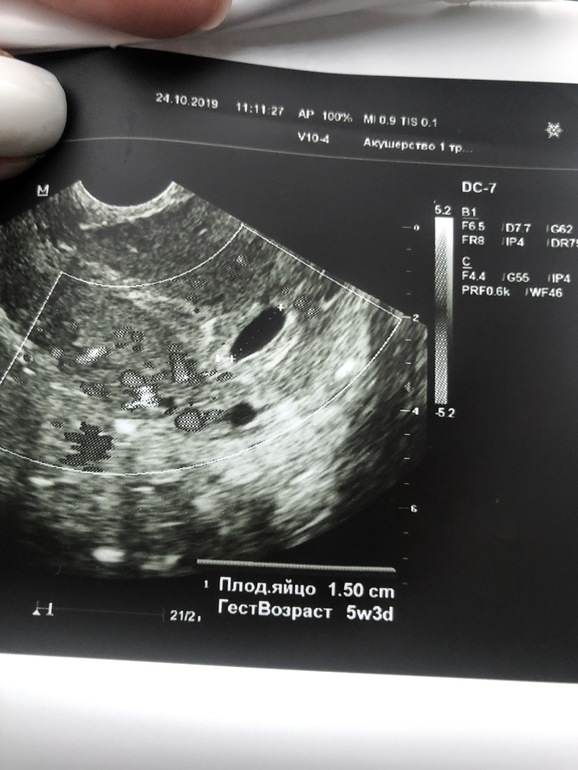

УЗИ, КТГ, доплер, скрининг, ХГЧ и другие анализыМилые,посмотрите ... мне врач нашла одно плодное яйцо и пустое говорит , срок по месячным 5.3 ,но дома я начала рассматривать снимки с узи и вот подумала ,не похоже ли это на 2 ПЯ ?

Вот снимок 2ПЯ в 5 недель 5 дней. При перемещении датчика контуры становились четкими. Который выше 15мм, который ниже 8мм. Может не стал специалист говорить "из благих побуждений", типа, чтоб не переживала, если маленькое ПЯ редуцируется. А, может, и правда, не ПЯ это вовсе(((

Ну я не переживаю на счёт эмбриональный,уверена что он появится . Меня смущает образование,похожее на второе яйцо )

Не знаю, что сказать. Ну с одной стороны похоже, но с другой контуры не такие четкие как у ПЯ, разница в размере большая. Мне кажется она бы сказала, если бы это было ПЯ.